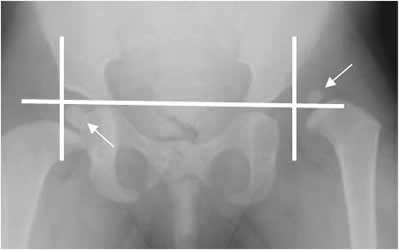

Angulo acetabular:

También conocido como ángulo de Hilgenreiner. Formado por la línea que une los cartílagos tri-radiados y su intersección con otra, que pasa por el borde acetabular externo. (1, 19). En la displasia es mayor de 35º. (19). (Fig 61 A y B).

Fig 61 A. Angulo acetabular.

Rx AP. Angulo derecho normal. Aumento del ángulo acetabular izquierdo, por displasia.

Fig 61 B. Displasia.

Rx AP. Incremento del ángulo acetabular (32º), por displasia.

Cuadrantes de Ombredanne:

Se traza una línea que pase por los cartílagos tri-radiados y otra vertical que cruce por el borde lateral del acetábulo. La cadera queda dividida en 4 cuadrantes y el núcleo de crecimiento normal, se localiza en el inferointerno. (19). En la displasia hay desplazamiento supero-lateral del núcleo de crecimiento de la cabeza femoral. (19).

(Fig 65).

Fig 65. Displasia de cadera.

Rx AP. Núcleo de crecimiento derecho, de localización normal, en el cuadrante inferoinfero. Desplazamiento superolateral del núcleo de crecimiento izquierdo, por displasia.